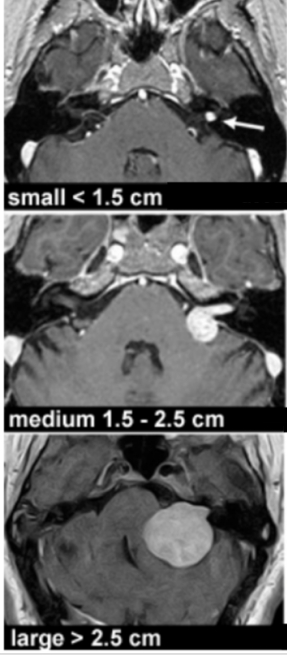

耳朵是我们听力和平衡的器官。它由三部分组成:外耳、中耳和内耳。中耳和内耳位于颅骨的颞骨深处。前庭耳蜗神经(八脑神经)负责将内耳的听觉和平衡信号传递到大脑。而随着听神经瘤的生长,它会从内部的听觉管扩展到脑干和被称为小脑桥角的骨头之间的空间。梨状瘤可继续扩大,压迫负责面部感觉的三叉神经。较终,肿瘤会压迫脑干。听神经瘤按其大小分为小(小于1.5厘米)、中等(1.5至2.5厘米)或大(大于2.5厘米)(下图)。